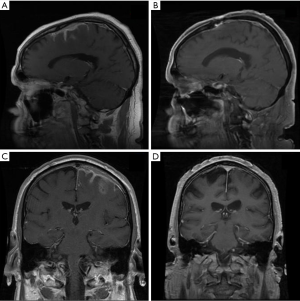

Primary dural lymphoma is an infrequent subtype of primary CNS lymphoma that arises from the dura mater without direct involvement of the parenchyma of the brain (Figure 7). Dural lymphoma are often mistaken for meningiomas due to similarities in radiographic features and clinical presentation (84). While the majority of primary CNS lymphomas are aggressive DLBCL, dural lymphoma are typically marginal zone lymphomas (85). Dural MALT lymphoma patients can present with a range of clinical symptoms; however, headache and seizures are common (86). A female predominance has been reported. Treatment approaches are varied; however, RT has been utilized with good outcomes (86,87). In a large series of 26 marginal zone dural lymphoma patients treated at MSKCC and the University of Miami, 22 patients achieved CR, including 12 patients treated with focal RT and 7 patients that received WBRT with or without a boost (88). Most patient were treated to a dose of 30–36 Gy. At a median follow up of just over 5 years, the median PFS and OS were not reached. All patients were alive at last follow up indicating the indolent nature of the disease and success of local therapy.

There is no standard approach for the management of MZL involving the dura, however aggressive systemic therapeutic approaches are often not warranted. In most cases the use of high dose methotrexate is discouraged, especially if RT is considered given the risk for neurotoxicity (88) and the excellent outcomes that can be achieved with single modality local therapy. Current guidelines from ILROG suggest focal therapy to the presurgical/biopsy MRI volume with margin to a dose of 30–36 Gy in cases of a single lesion (15). For multifocal disease WBRT to 24 Gy followed by a boost to involved sites with an additional 12 Gy is considered appropriate therapy. It is likely that lower RT doses such as 24 Gy would be effective, however existing published data indicates good outcomes of moderate RT doses of 30–36 Gy.